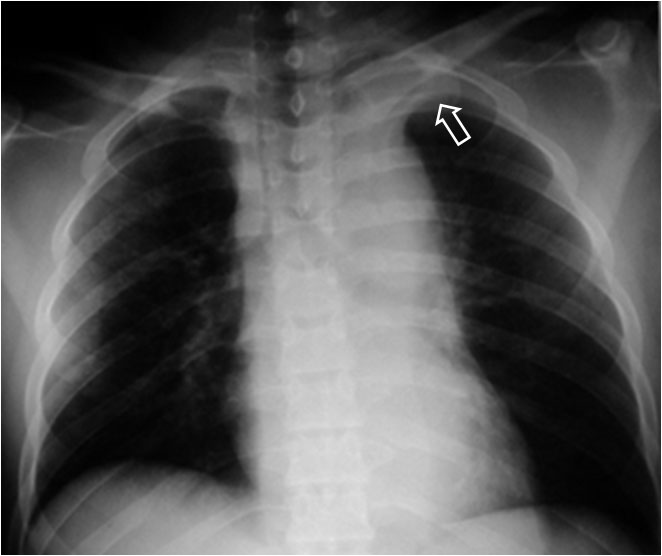

La aparición de una densidad en el ápex pulmonar izquierdo, de borde inferior cóncavo y bien delimitado (casquete apical) en un paciente con traumatismo torácico, debe hacernos sospechar la existencia de una rotura aórtica.

Deben excluirse otras causas de casquete apical, especialmente las lesiones residuales tuberculosas, que suelen acompañarse de otros hallazgos como tractos fibrosos pleuro-parenquimatosos, pérdida de volumen en el lóbulo superior, granulomas, etc.

Mostramos un caso de rotura aórtica por accidente de moto. En este paciente también aparece el signo de la alteración del contorno aórtico.